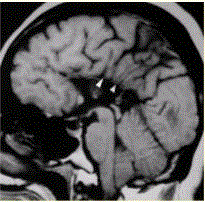

问题 患者女,43岁。智力低下。MRI结果如下图所示。 关于该病的描述,错误的是

选项 A.常与其他畸形伴发,如前脑无裂畸形、Chiari畸形、胼胝体脂肪瘤等 B.均为全部缺如 C.矢状位显示最佳,无胼胝体结构 D.脑回放射状排列,指向侧脑室 E.影像学首选MR矢状面、冠状面

答案 B